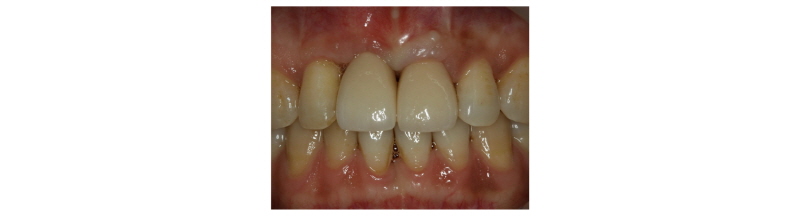

A 39-year-old male patient visited to the KyungHee University Dental Hospital with periapical abscess in the right maxillary central incisor. After clinical and radiographic examination, the tooth was planned to be extracted. The patient didn’t want to prepare the additional adjacent teeth. The right maxillary central incisor was planned to restore implant restoration and the left maxillary central incisor decided to proceed re-endodontic treatment and crown restoration (Fig. 1). Because of relatively young age of the patient, there was a lot of interest in esthetic results. Therefore, we planned to make provisional implant restoration and make a definitive prosthesis duplicating the emergence profile of the provisional restoration, and planned to use zirconia abutment when restoring the definitive prosthesis. First, preparation of maxillary left central incisor was done and maxillary right central incisor was extracted and cantilever provisional restoration was restored (Fig. 2, 3). Re-endodontic treatment of maxillary left central incisor was also progressed. After 3 months healing periods, implant placement was planned under evaluation of cone beam computed tomography scan with radiographic stent (Fig. 4). Implant placement was guided by surgical stent with bone graft (Bio-oss, Geistlich Pharma AG, Wolhusen, Switzerland) (Fig. 5, 6) and there were no systemic diseases would become problematic for implant surgery. Clinical and radiographic evaluation neither described any obvious active infection. Internal submerged type implant (4.0 mm×12.0 mm Implantium, Dentium, Korea) was placed and healing abutment was tightened. After surgery, provisional restoration was modified (Fig. 7). 3 months after implant surgery, fixture level impression was taken using pick-up impression coping (DPU 40 15 HL, Dentium, Korea) for provisional restoration (Fig. 8). Then, provisional crown with plastic provisional abutment (RAB 45 20 PHL, Dentium, Korea) was set for gingival molding (Fig. 9). During 3 weeks of provisional restoration period, the patient was satisfied with the function and the appearance of the provisional restoration. To transfer the emergence profile of provisional restoration, transfer technique was used with polyvinyl-siloxane impression material (Silagum, light body and putty, GmbH, Germany) (Fig. 10) and impression coping was modified. The final fixture level impression was taken using polyvinyl-siloxane impression material (Express light body and regular body, 3M ESPE, St Paul, MN, USA) after connection of modified pick-up impression coping (Fig. 11). A CAD/CAM zirconia abutment was milled and abutment adapted. Resin material (Pattern Resin LS; GC, America) and wooden sticks were used for delivery to laboratory of anterior teeth horizontal line. Midline also marked (Fig. 12). Splinted porcelain fused to zirconia prosthesis was fabricated. The root of the maxillary left central incisor being short and the prognosis being poor, so the crown was splinted with the maxillary right maxillary incisor implant prosthesis. The definitive crown and abutment were delivered to patient (Fig. 13). The esthetic, marginal fit was evaluated and the zirconia abutment was tightened to 30 Ncm using torque controller and splinted maxillary right and left definitive prostheses was set final cementation with resin-modified glass ionomer cement (FujiCEMTM, GC, Japan). Within the 3 years follow-up after treatment, the patient satisfied with the functional and esthetic outcomes, and the gingival architecture preserved that form.

This clinical report demonstrates esthetic treatment outcome of maxillary right and left central incisor using emergence profile transfer technique and zirconia abutment and porcelain fused to zirconia crown. By connecting implant to natural tooth, the favorable clinical outcome is achievable, with fair long-term prognosis.